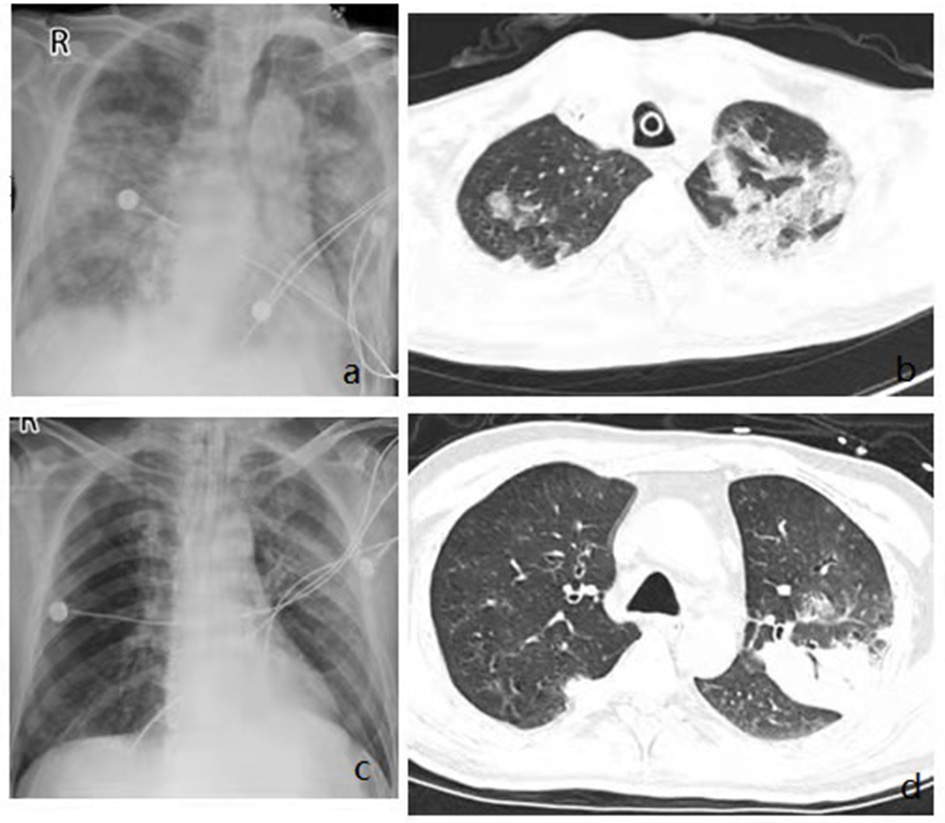

The general condition and clinical characteristics of the patients with adenovirus-associated ARDS and non-adenovirus associated ARDS are shown in Table 1. The mean age was 54.93 ± 19.04 years among the adenovirus-associated ARDS patients, younger than that of the non-adenovirus associated ARDS patients. Among the adenovirus-associated ARDS patients, 78.57% were males, 50% were smokers, and 71.43% had high nutritional risk (Table 1). In addition, 28.57% of the adenovirus-associated patients had concurrent lung diseases, and 28.57% of the patients also had an immunodeficiency. All patients had cough, sputum expectoration, and shortness of breath, and 92.86% of them had a fever. Most patients presented with a low-grade fever. As shown in Table 2, the PaO2/FiO2 for 64.29% of the adenovirus-associated patients was between 150 and 200 mmHg. Most of the patients had normal blood CO2, manifesting as type I respiratory failure. The average time from the onset of shortness of breath to tracheal intubation was 24 h. Hypoproteinemia occurred in 85.71% of the adenovirus-associated ARDS patients, and abnormal coagulation function occurred in >60% of the patients. At the time of enrollment, 64.29% of the patients had a low total number of white blood cells, and more than 70% of the patients had a decrease in the total number and percentage of lymphocytes. Additionally, 85.71% of the adenovirus-associated patients had a significant decrease in the number of CD3+CD4+ T cells and higher serum creatinine during the early stage compared with the non-adenovirus associated ARDS patients. Most of the adenovirus-associated patients had diffuse infiltrates in both lungs. Three (21.43%) of the patients had interstitial abnormalities. Five patients (35.71%) had pleural effusions. Only a few patients showed ground-glass opacity (Figure 3).

Figure 3

Imaging findings showing diffuse multifocal or diffuse opacity. Chest x rays from admission showing bilateral diffuse infiltrates (a,c), Chest CT from admission showing multifocal consolidation and groundglass opacity in both lungs (b,d).